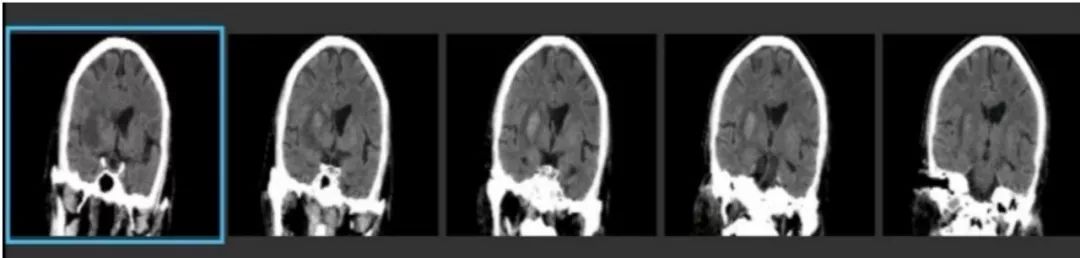

术前CT

术前MR

ASPECTS评分 8分

术前造影:

串联病变

双颈动脉支架

术后CT

24H

36H

45H